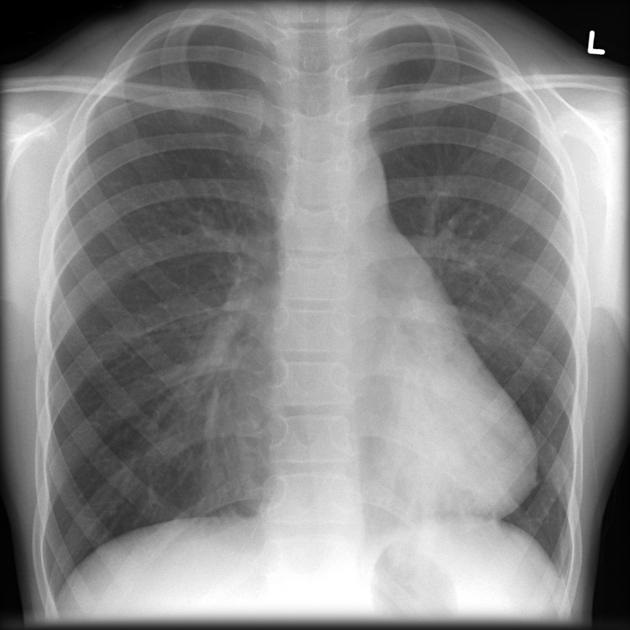

Image radiologique analogue du pectus excavatum

sur plain film PA / AP pulmonaire :

Image

radiologique analogue du pectus carinatum sur plain film PA /

AP pulmonaire :

-

Augmentation du diametre antero- posterieure du thorax

Deformation en deux forme : forme chondrogladiator (

angle de prostruction est en inferieure du sternum } et

chondromadibrual ( angle de prostruction est en

superieure du sternum }

radiologique TDM et IRM du pectus excavatum et carinatum :

Index Haller ( diametre

transverse maximale / diametre antero-posterieure du

thorax sur deux plain film AP et profile ) est de plus

3.25 en cas pectus excavatum . Nomalement etre de

moindre de 2 .

Angle de torsion du sternum

de plus 30 degree est egale d'agravation du pectus

excavatum

Indice de corection ( IC )

du thorax normale est 10 . De moindre est pectus

excavatum ..